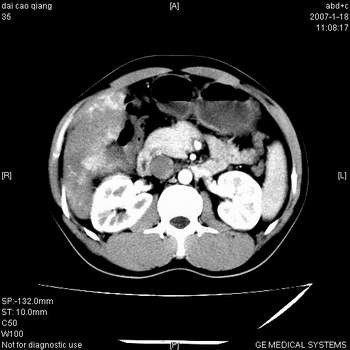

符合巨块型肝癌表现:

1、平扫低密度,增强后表现为快进快出。

2、动脉期可见迂曲的动脉供血血管

3、并可见门静脉右支癌栓形成

4、可见假包膜

5、腹主动脉旁结节影,考虑肿大淋巴结。

肝右叶巨大不均匀低密度肿块,前缘有假包膜,增强明显的呈快进快出表现,门脉右支有癌栓,病人虽然年轻但还是首先考虑肝右叶巨块形肝癌,病人血象高只能说有合并感染。不支持肝脓肿。